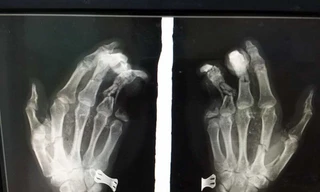

Từ khóa: "mất 2 đốt ngón tay"

1 kết quả